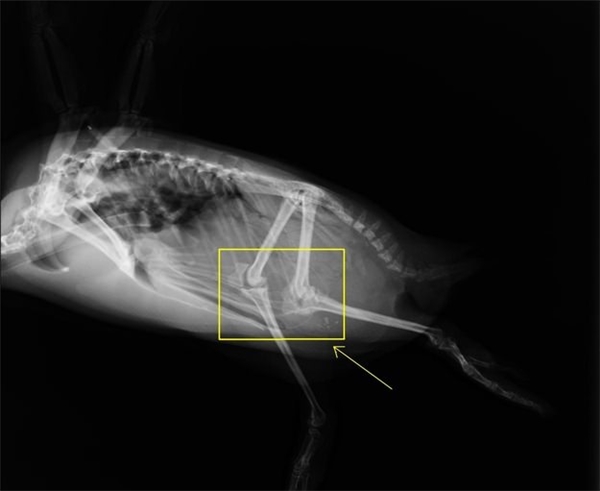

6. Chim cánh cụt không chân ngắn như mọi người vẫn tưởng

Cách di chuyển của cánh cụt trông lạch bạch buồn cười và đáng yêu thế thôi nhưng trên thực tế người ta có đầu gối và chân lại còn dài miên man nữa đấy.

Đầu gối của chim cánh cụt được giấu dưới lớp lông dày của nó.